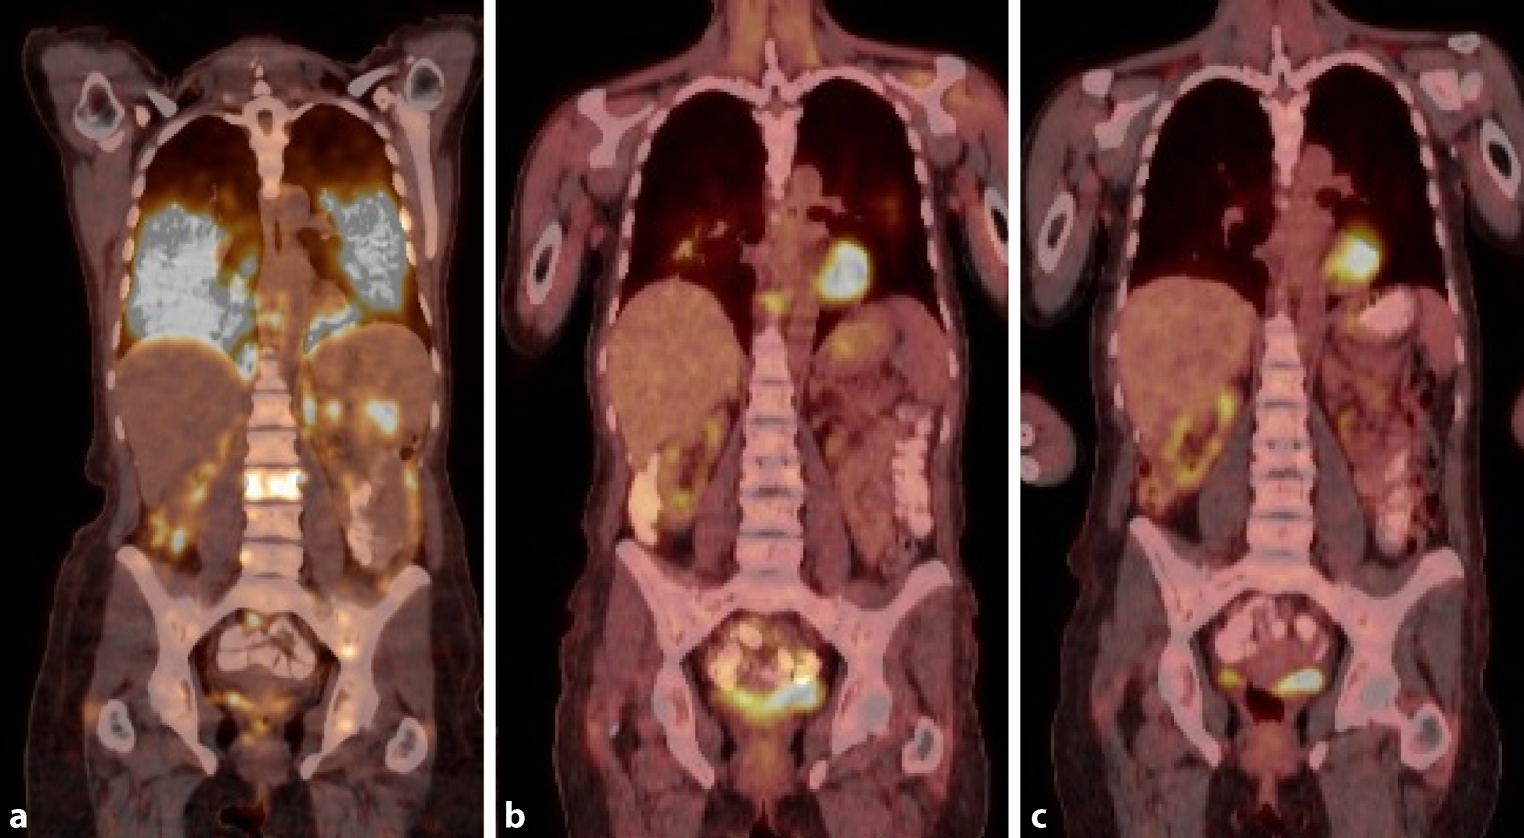

In fluorodeoxyglucose positron emission tomography computed tomography (FDG PET CT) neoplastic retention was shown in countless, disseminated pulmonary, peritoneal, osseous and lymphatic lesions (Fig. 2a). Aspiration biopsy from the right lower lobe was conducted by means of bronchoscopy (Fig. 3a). However, cytology could not affirm malignant cells and testing for tumor markers was negative. Finally, a cervical lymph node was extirpated for further analysis. Immunohistochemistry revealed dense foci of CD68-positive histiocytic tumor cells and multinuclear giant cells of Langerhans type (Fig. 3b). Staining for TTF‑1, p40, Melan‑A, HMB45, CD20, CD3, CD21 and CD123 was negative; however S100 and CD1a were positive (Fig. 3c,d). Meeting the criteria of malignant cells, the scarce diagnosis of Langerhans cell sarcoma was made. FoundationOne® analysis revealed genomic alterations in MAP2K1 (MEK1), PTEN (loss), CXCR4, FAS (loss exons 2–9), SMARCA4, TNFRSF14 and TP53 without therapeutic implication. Tumor mutation burden (TMB) was low and BRAF was wildtype. Ki-67 accounted for 70% correlating with a rapid clinical course of disease. A transfer to our department took place after lymph node extirpation. From date of first presentation to introduction of therapy (lagtime 40 days), the patient developed an oxygen demand of six liters per minute.

Fig. 2

Course of disease remission delineated by whole body fluorodeoxyglucose positron emission tomography: a at initial diagnosis, disseminated pulmonary metastases; b after one cycle of chemotherapy, partial remission; c one year after high-dose chemotherapy with autologous stem cell transplant, complete remission

Considering the young patient age, good pre-existing general condition and disseminated illness, we decided for subsequent polychemotherapy and stem cell transplantation. In September 2017, the patient received a preliminary phase with vinblastine (3 mg/m2 on day 1) and dexamethasone (40 mg on days 1–3), followed by primary chemotherapy with six cycles of cyclophosphamide (750 mg/m2 on day 1), doxorubicin (50 mg/m2 on day 1), vincristine (1.4 mg/m2 on day 1), and prednisolone (40 mg/m2 on days 1–5) (CHOP). The first cycle already led to a good partial remission (Fig. 1b and 2b); oxygen demand was reduced to two liters per minute. After reaching complete remission and successful stem cell apheresis, high-dosage therapy with carmustine (300 mg/m2 on day 1), cytarabine (400 mg/m2 on days 2–5), etoposide (200 mg/m2 on days 1–5), and melphalane (120 mg/m2 on day 6) with subsequent autologous stem cell transplantation was administered in May 2018. At the present time, one year later, the patient is in excellent general condition without oxygen demand and complete remission is still persisting (Fig. 1c and 2c).